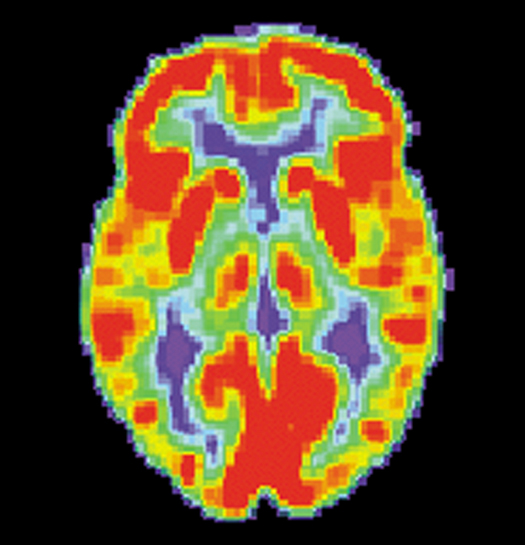

It’s called transcranial direct-current stimulation (tDCS), and over the last decade many in the scientific and medical world have been abuzz about its potential to treat some diseases and mental illnesses. Meanwhile, an enthusiastic community of DIY “brain hackers” has adopted tDCS as a way to boost their cognitive powers.

Part of the appeal of tDCS is its simplicity: Two electrodes are placed on the head, and a low-intensity current generated by a basic, battery-powered device is passed through the brain for a set period of time. The current isn’t strong enough to cause neurons to fire, but it changes the “resting membrane potential” of neurons, meaning that it can make neurons more or less likely to fire. Depending on the polarity of the current, it can be used to increase or decrease neuron excitability.